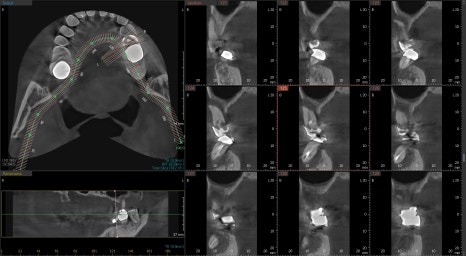

23.08.25 — 상악동 거상술 전 / 23.11.10 — 시술 후

발치 후 6개월 뒤 내원 시 안쪽 뼈 상태가 좋지 않아 뼈이식과 상악동 거상술이 모두 필요한 상황이었습니다. CT 화면을 직접 보여드리며 근거를 설명드린 뒤, 위쪽을 먼저 진행했습니다.

3D CT를 통해 신경 위치, 뼈의 두께와 밀도, 상악동과의 거리까지 종합 분석한 뒤, 어느 각도로 얼마나 깊이 심을지 미리 설계하고 진행합니다. 특히 뼈이식과 상악동 거상술이 필요한 복잡한 케이스일수록 이 설계 과정이 더욱 중요합니다.

23.04.25 (치료전)- 24.09.04 (치료후)